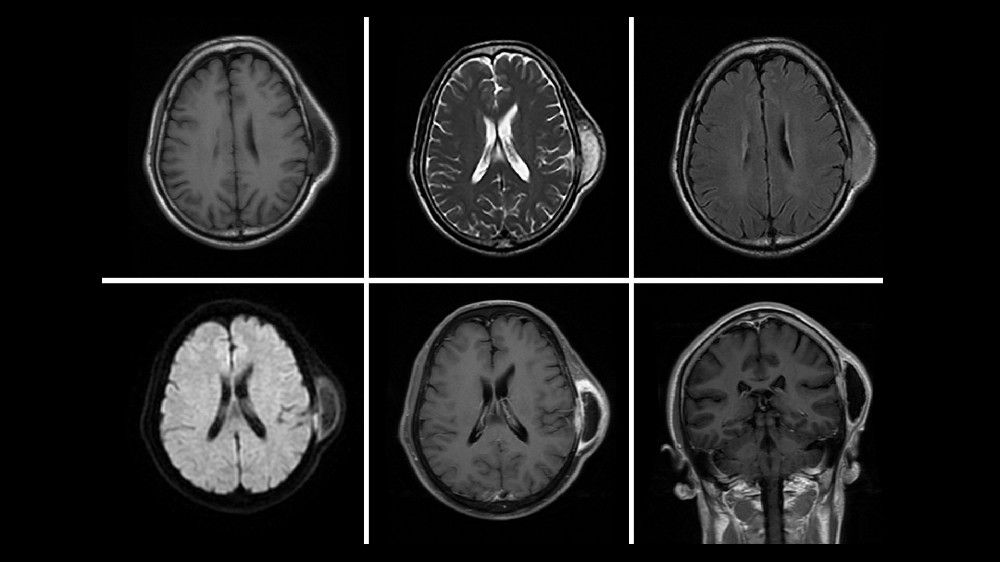

早期發現對於改善預後和治療效果至關重要。定期篩檢,例如超音波或磁力共振掃描,特別是對於有遺傳傾向的族群,可支援早期診斷,顯著提高治療效果。all cancers的「先治癒,後付款」政策強調以病患為中心的及時篩檢,確保財務上的壓力絕不會影響及時檢測和全面管理如橫紋肌肉瘤等疾病。